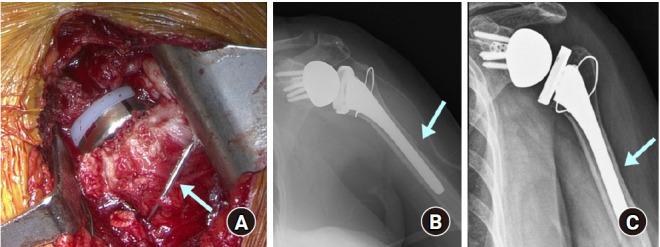

Reverse shoulder arthroplasty is an ideal treatment for glenohumeral dysfunction due to cuff tear arthropathy. As the number of patients treated with reverse shoulder arthroplasty is increasing, the incidence of complications after this procedure also is increasing. The rate of complications in reverse shoulder arthroplasty was reported to be 15%-24%. Recently, the following complications have been reported in order of frequency: periprosthetic infection, dislocation, periprosthetic fracture, neurologic injury, scapular notching, acromion or scapular spine fracture, and aseptic loosening of prosthesis. However, the overall complication rate has varied across studies because of different prosthesis used, improvement of implant and surgical skills, and different definitions of complications. Some authors included complications that affect the clinical outcomes of the surgery, while others reported minor complications that do not affect the clinical outcomes such as minor reversible neurologic deficit or minimal scapular notching. This review article summarizes the processes related to diagnosis and treatment of complications after reverse shoulder arthroplasty with the aim of helping clinicians reduce complications and perform appropriate procedures if/when complications occur.